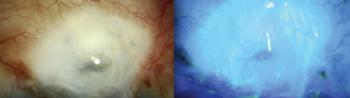

Ophthalmologists can opt to use vital stains for cultures and corneal scrapings.